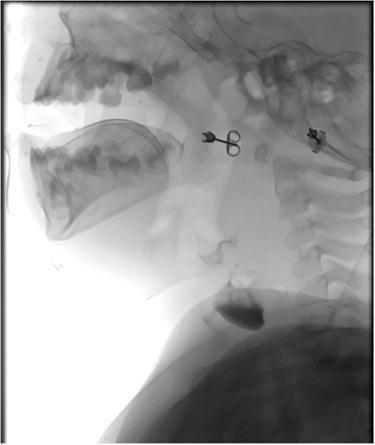

Congenital oesophageal diverticulum is incredibly rare and has not commonly been published in the literature. Oesophageal diverticulum can be asymptomatic; however, symptoms such as dysphagia, regurgitation and chest discomfort may be present. We describe the case of a paediatric patient presenting with biphasic stridor, respiratory distress and cyanosis at birth, who was found to have a supraglottic cyst and later the presence of an oesophageal diverticulum shown on ultrasound imaging. There has been one other case reported in the literature of an oesophageal diverticulum presenting with stridor, and we therefore believe this is one of only two cases to illustrate this atypical presentation of congenital oesophageal diverticulum. It highlights the importance of a meticulous multidisciplinary team approach to patient care, as well as conducting appropriate investigations to aid early diagnosis to improve patient outcomes.